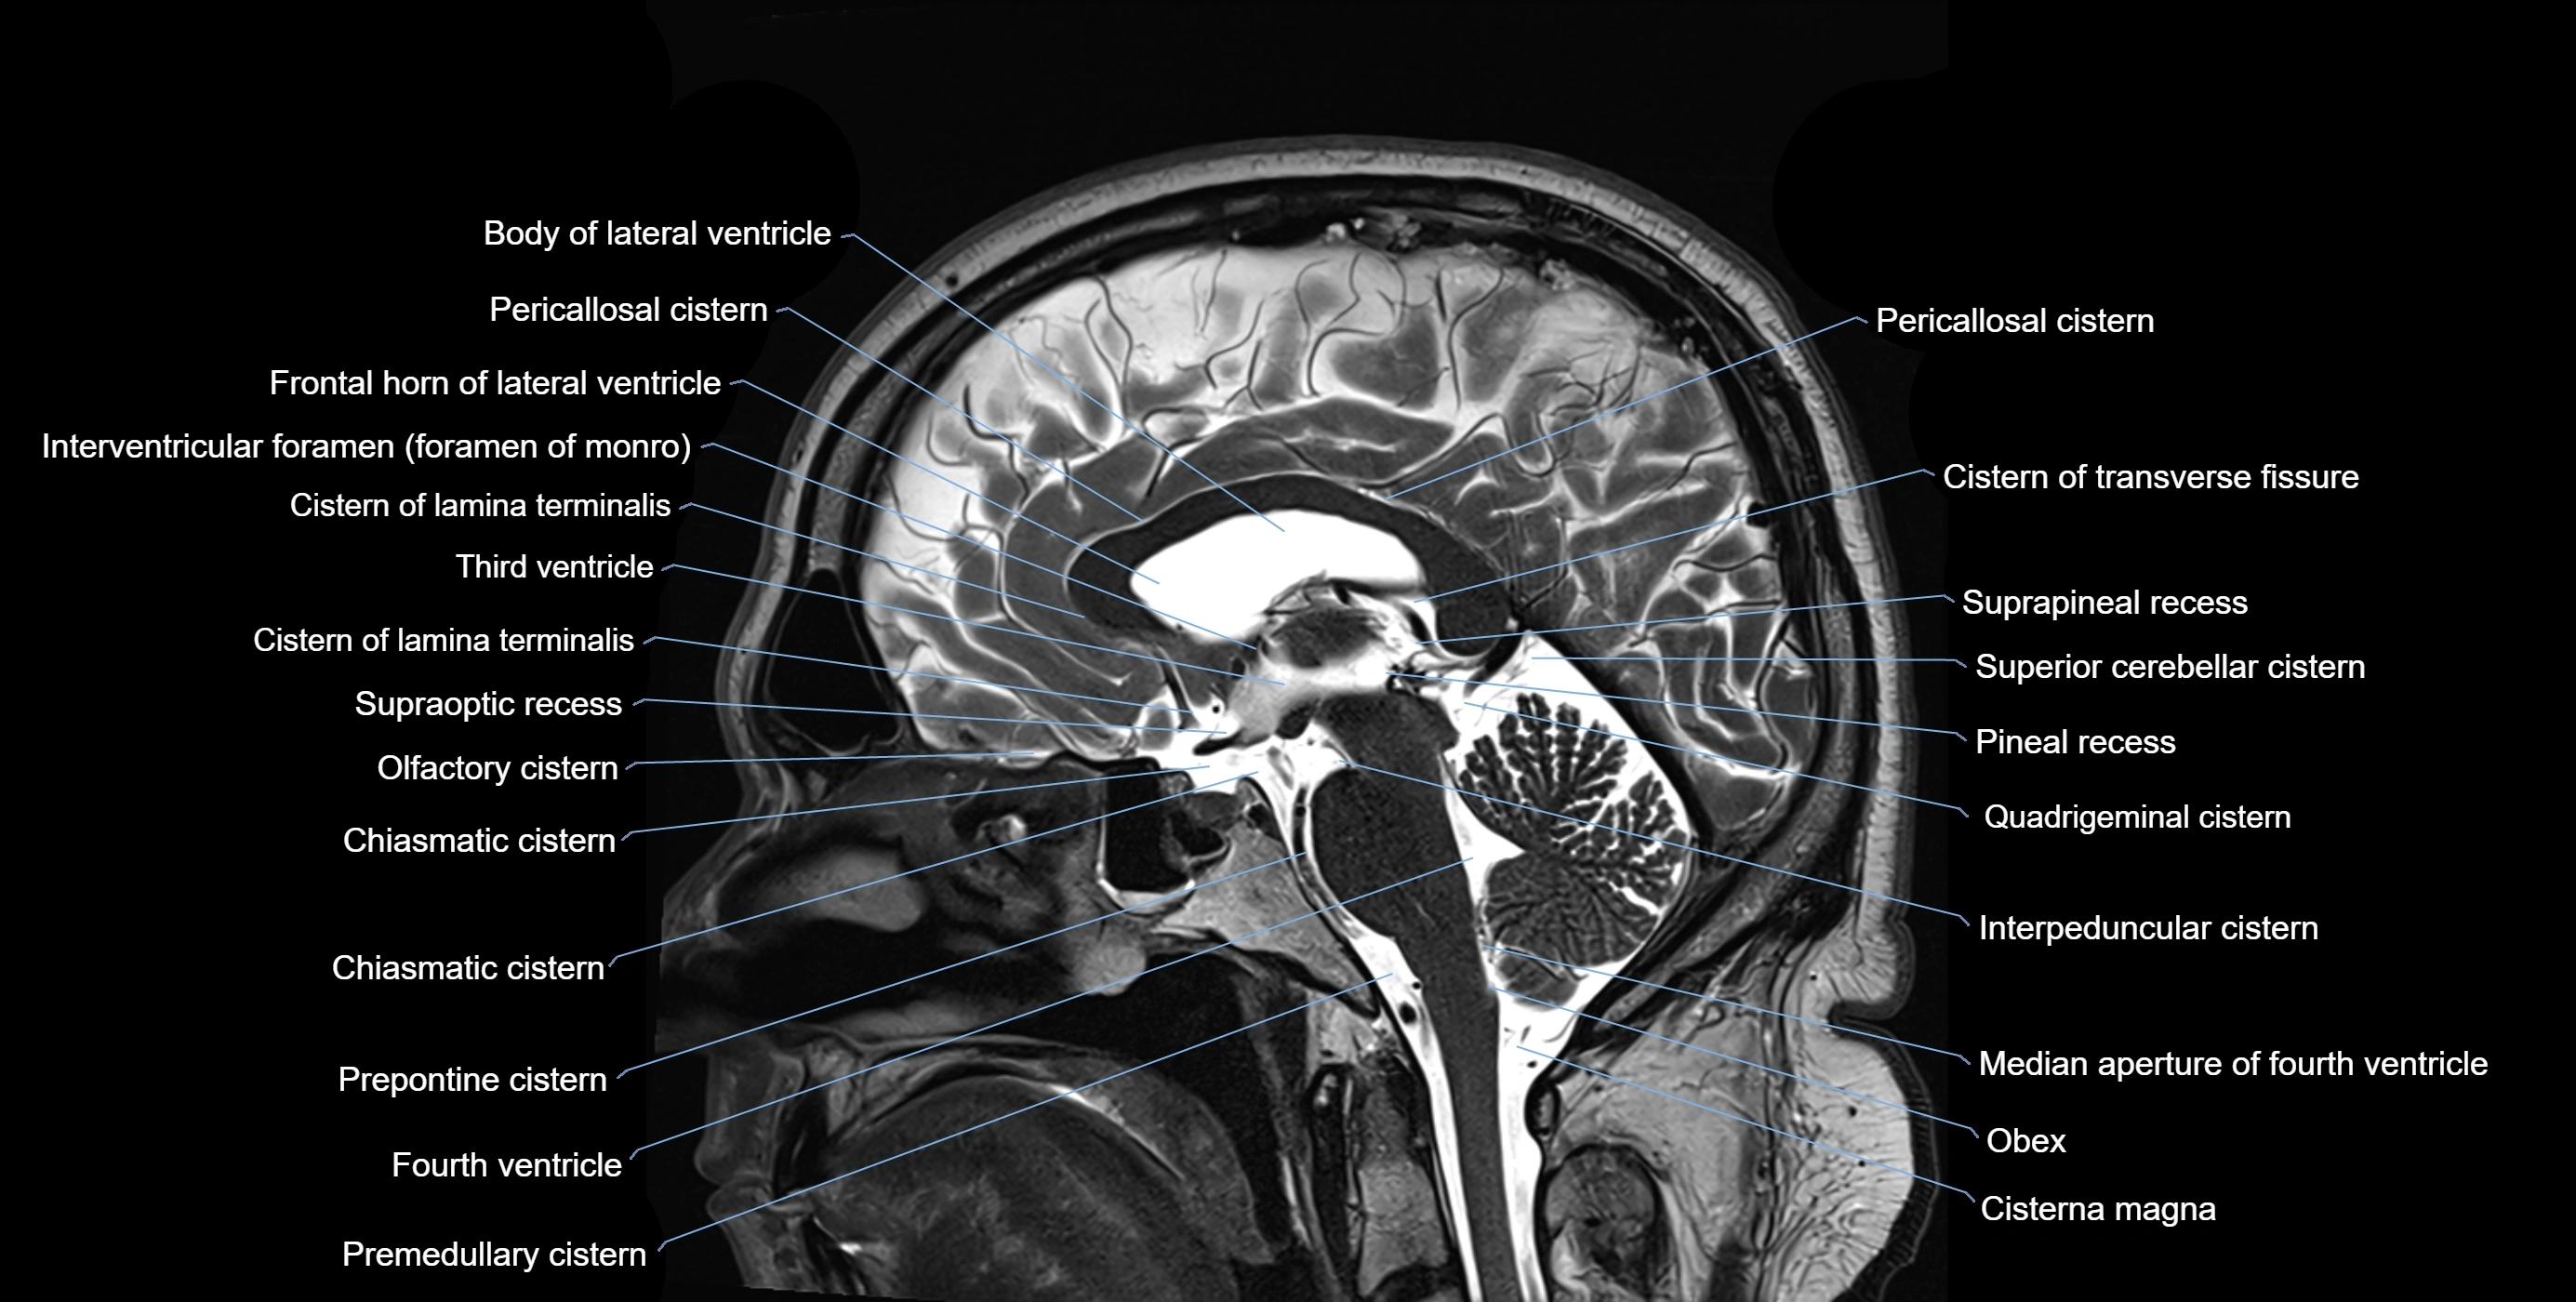

MRI images

image